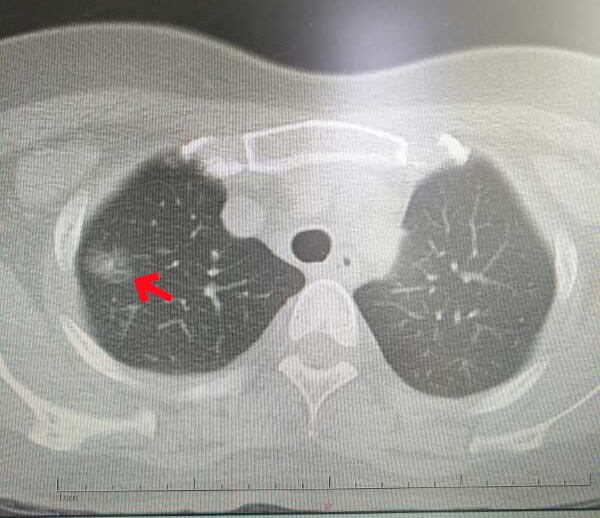

检查所见:

右肺上叶尖后段磨玻璃密度影,直径约15mm,手术证实肺微浸润腺癌。